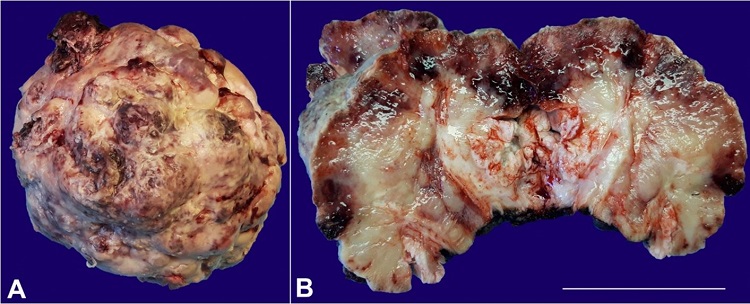

A 75-year-old man underwent partial penectomy as a consequence of a large penile mass. Grossly, an exophytic and gray mass with 9.0x8.2x7.5cm was identified, involving the glans. The cut surface was gray and white with congestive areas (Figure 1).